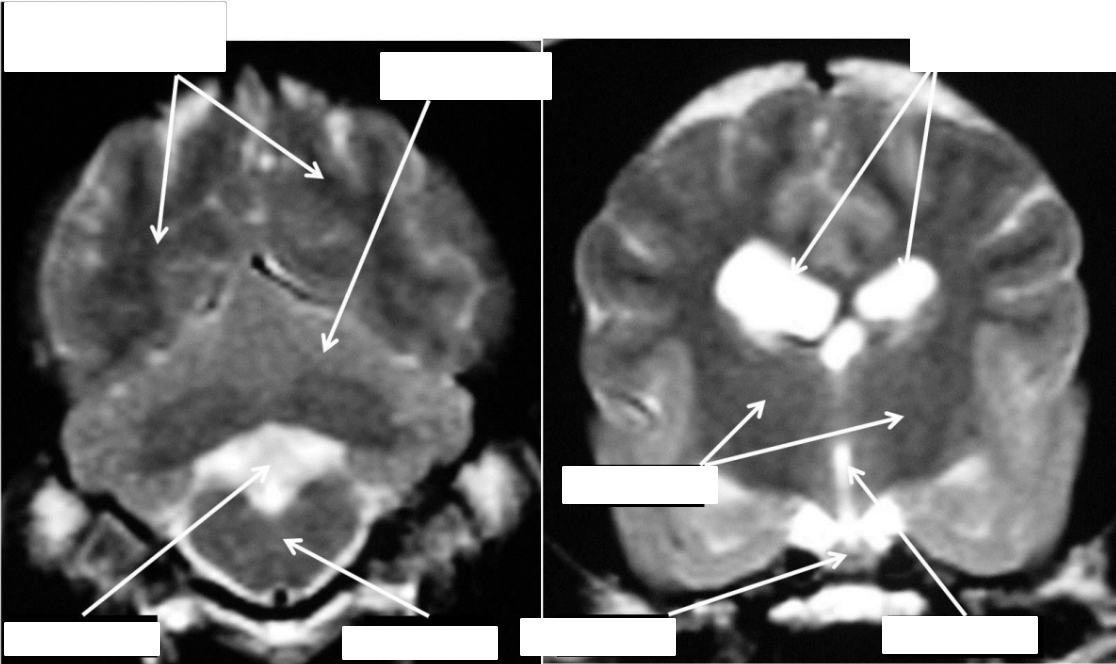

identify the lateral ventricles, pituitary, cerebellum, cerebral hemispheres, brainstem, eyeballs

how does fluid appear on T1w and T2w scans

T1w = hyperintense

T2w = hypointense

identify the structures

what are the species differences between cat and dog (shape, proportional sizes of the cerebral hemispheres and cerebellum)

the lateral ventricles are smaller in cats than in dogs